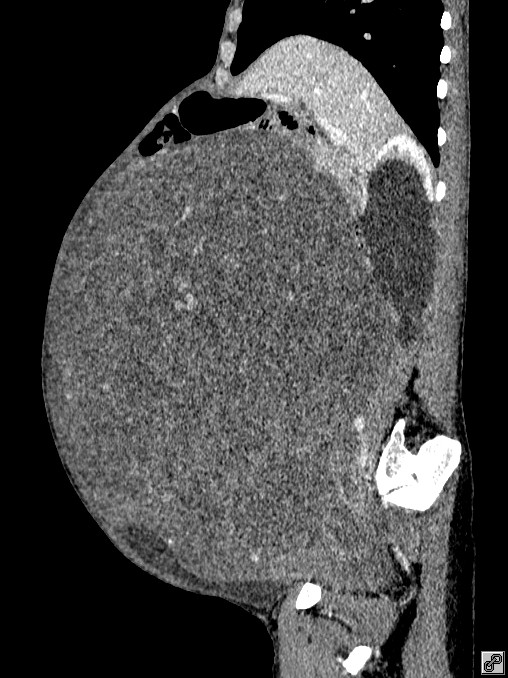

意识到有问题,家人赶紧带着王阿姨来到广医三院看病。随后,检查结果震惊了家人——王阿姨的子宫长了一个巨大的肿物,占满了整个盆腹腔!医生初步判断可能是子宫肌瘤。

手术前患者的CT影像图。

“子宫肌瘤很常见,但如此巨大的肌瘤比较少见”接诊的妇科主任生秀杰介绍:“巨型肿物在盆腔内生长,不停‘吸取’身体的营养,让身体长期处于消耗状态,导致了患者越来越消瘦。此外,肿物也压迫影响了盆腹腔多个脏器,如果继续发展,很可能进一步膈肌上抬,患者呼吸都会受限。”